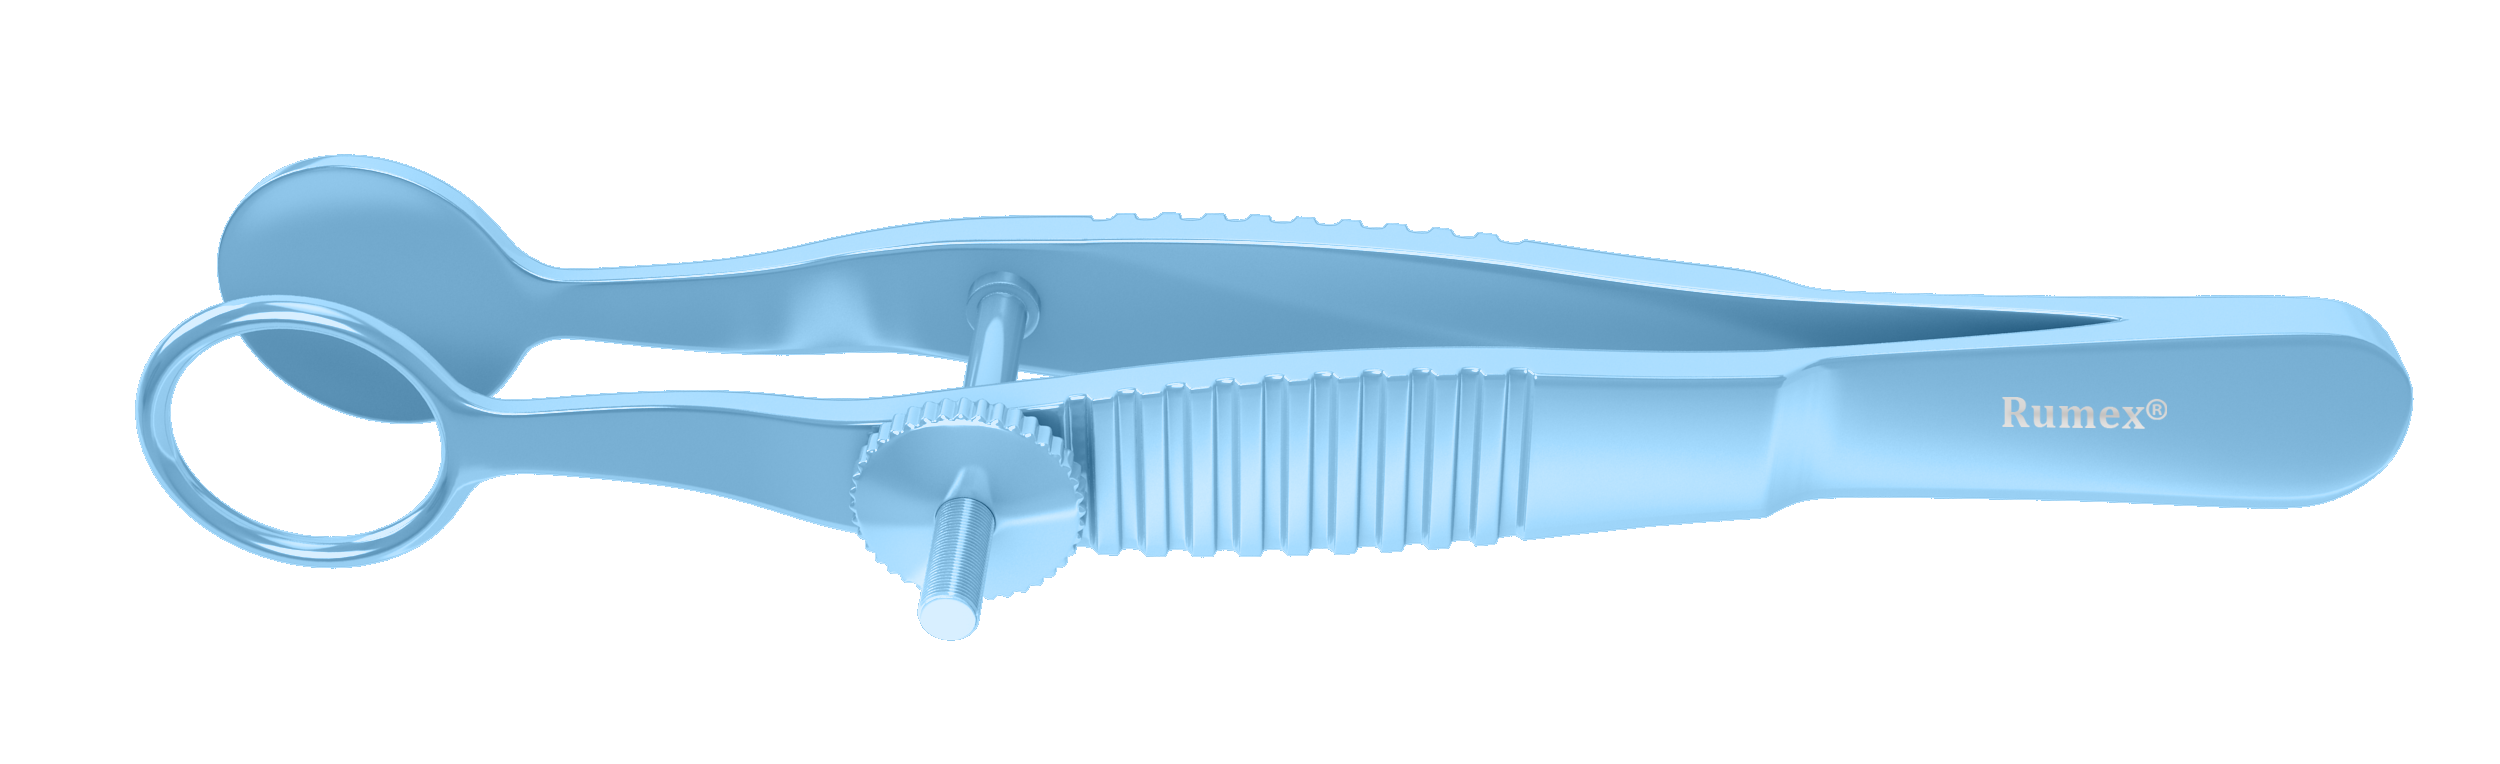

Rumex Lambert Chalazion Forceps, Medium, 12.00 mm Diameter, Length 97 mm, Titanium, 4-1909T

12.00 mm internal diameter of the upper plate. Designed to evert the eyelid. The ring blade surrounds the lump to expose chalazion for drainage and removal. Solid lower plate. Locking thumb screw mechanism.